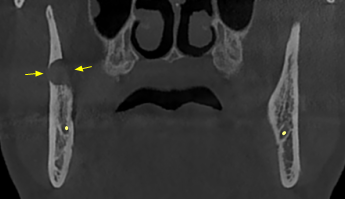

Ο ασθενής παραπέμφθηκε από τον οδοντίατρό του για περαιτέρω αξιολόγηση των ευρημάτων με Υπολογιστική Τομογραφία Κωνικής Δέσμης (CBCT).

Το CBCT αποκάλυψε την παρουσία εκτεταμένης υπόπυκνης αλλοίωσης στην οπίσθια δεξιά περιοχή της κάτω γνάθου οπισθίως των υπαρχόντων δοντιών η οποία είχε προκαλέσει εκτεταμένη έκπτυξη, λέπτυνση και λύση των συμπαγών πετάλων, ενώ είχε απωθήσει και τον πόρο του κάτω φατνιακού νεύρου προς τα κάτω.

CBCT 12/2020